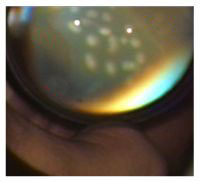

Imagen Fondo de ojo con Lupa de 28 D durante el tratamiento con láser. Los spots de láser deben ser aplicados en forma semiconfluente.